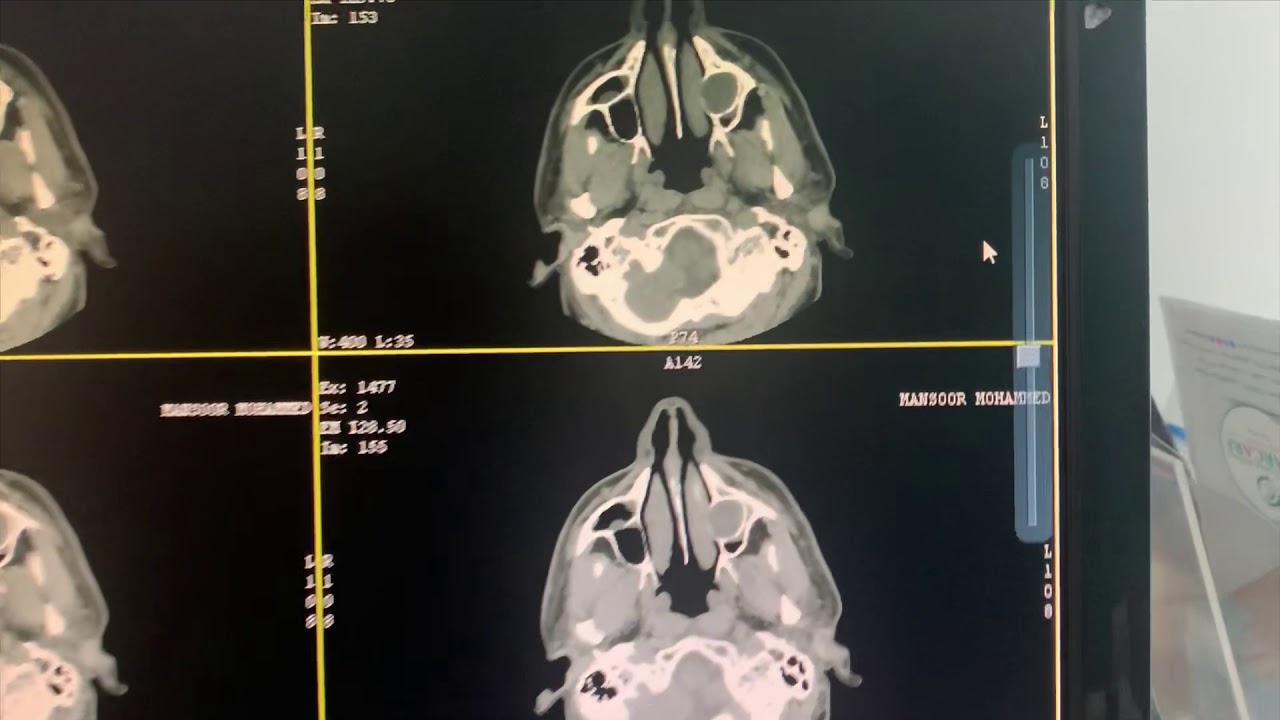

Large dental and maxillary cyst extending into the sinus and nasal lateral wall surgically removed

Large dental and maxillary cyst extending into the sinus and nasal lateral wall surgically removed This large #cyst has been beautifully removed under general anesthesia by dr sunil Richardson and his team.